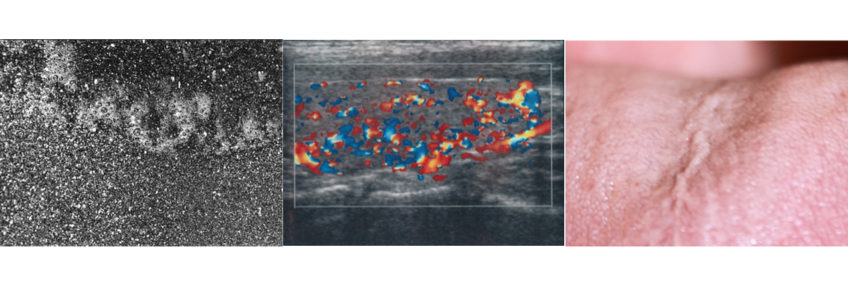

Il lavoro “In corpore” nasce come un’esplorazione del corpo umano come la parte più vicina a noi che abitiamo da sempre e che, al suo interno, ha le sembianze di un pianeta estraneo.

In questo progetto affianco fotografie di paesaggi terrestri, marini o lunari e fotografie di frazioni di corpi o immagini satellitari a scansioni interne al mio corpo: ecografie, risonanze, misurazioni a onde elettromagnetiche, analisi cromosomiche, doppler e radiografie. Nel corso dell’ultimo anno ho dovuto fare moltissime analisi ed ero molto incuriosita dalle sembianze che l’interno del mio corpo assumeva a seconda del tipo di indagine che veniva eseguita. Durante un eco-doppler delle vene guardavo nello schermo dello studio medico quella che sembrava una sonda spaziale che sorvola un pianeta extraterrestre, così è nato questo progetto in cui il corpo diventa un vero e proprio luogo da esplorare, protagonista di un viaggio alla scoperta di un’interiorità sconosciuta.